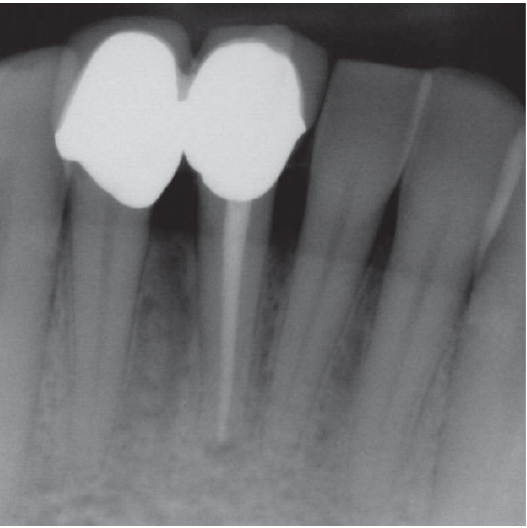

After

After Root Canal treatment